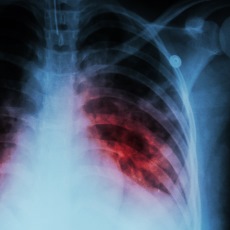

- Tests for TB disease in the lungs usually include testing samples of your sputum and having chest x-rays.

- Pulmonary tuberculosis (Medical Encyclopedia) Also in Spanish